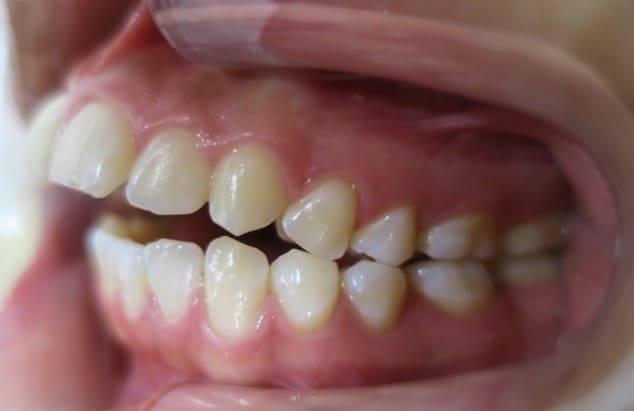

● C4を超え歯根までの虫歯を抜歯、親知らずを利用して歯並び全体を整えた症例

藤沢デンタルオフィスの虫歯や破折で抜歯後の部分矯正